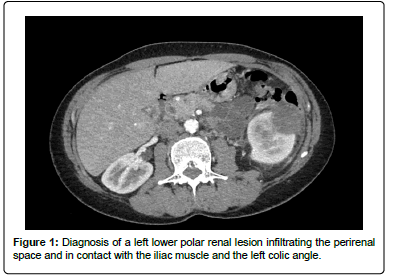

A 54-year-old woman with no notable medical history except for a total conservative hysterectomy, surgery for bilateral hallus valgus, and lipoma removal was referred to our institution in November 2020 for the exploration of nausea, vomiting and hyperleukocytosis. Abdominal CT scan identified a left lower polar renal lesion measuring (52 × 52 × 57) mm, infiltrating the perirenal space and in contact with the iliac muscle and the left colic angle (Figure 1).